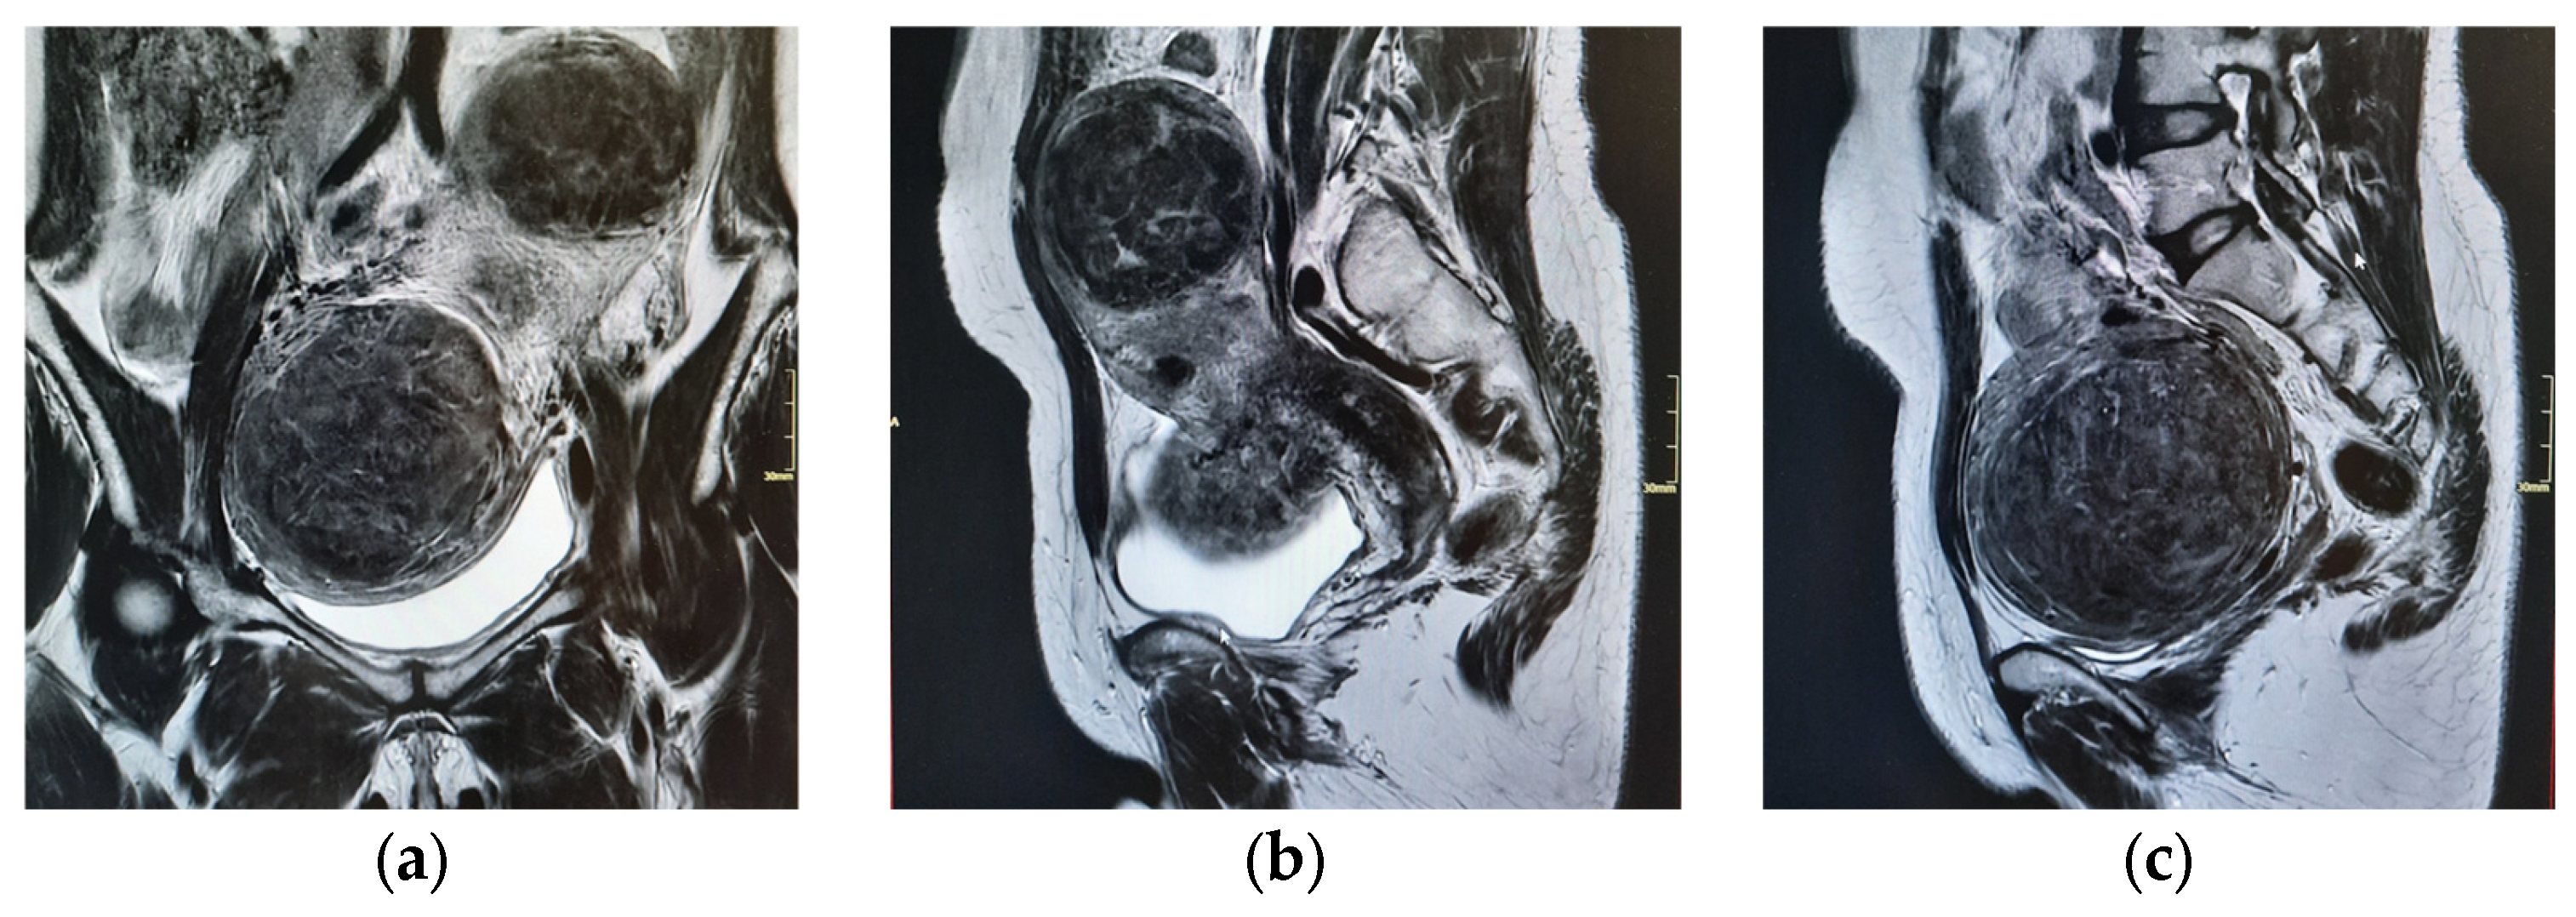

| 15 April 2025 | Pelvic MRI confirms multiple intramural and submucosal fibroids; significant uterine deformation. |

| 9 May 2025 | Informed consent for open multiple myomectomy; multidisciplinary decision to perform PUAE preoperatively. |